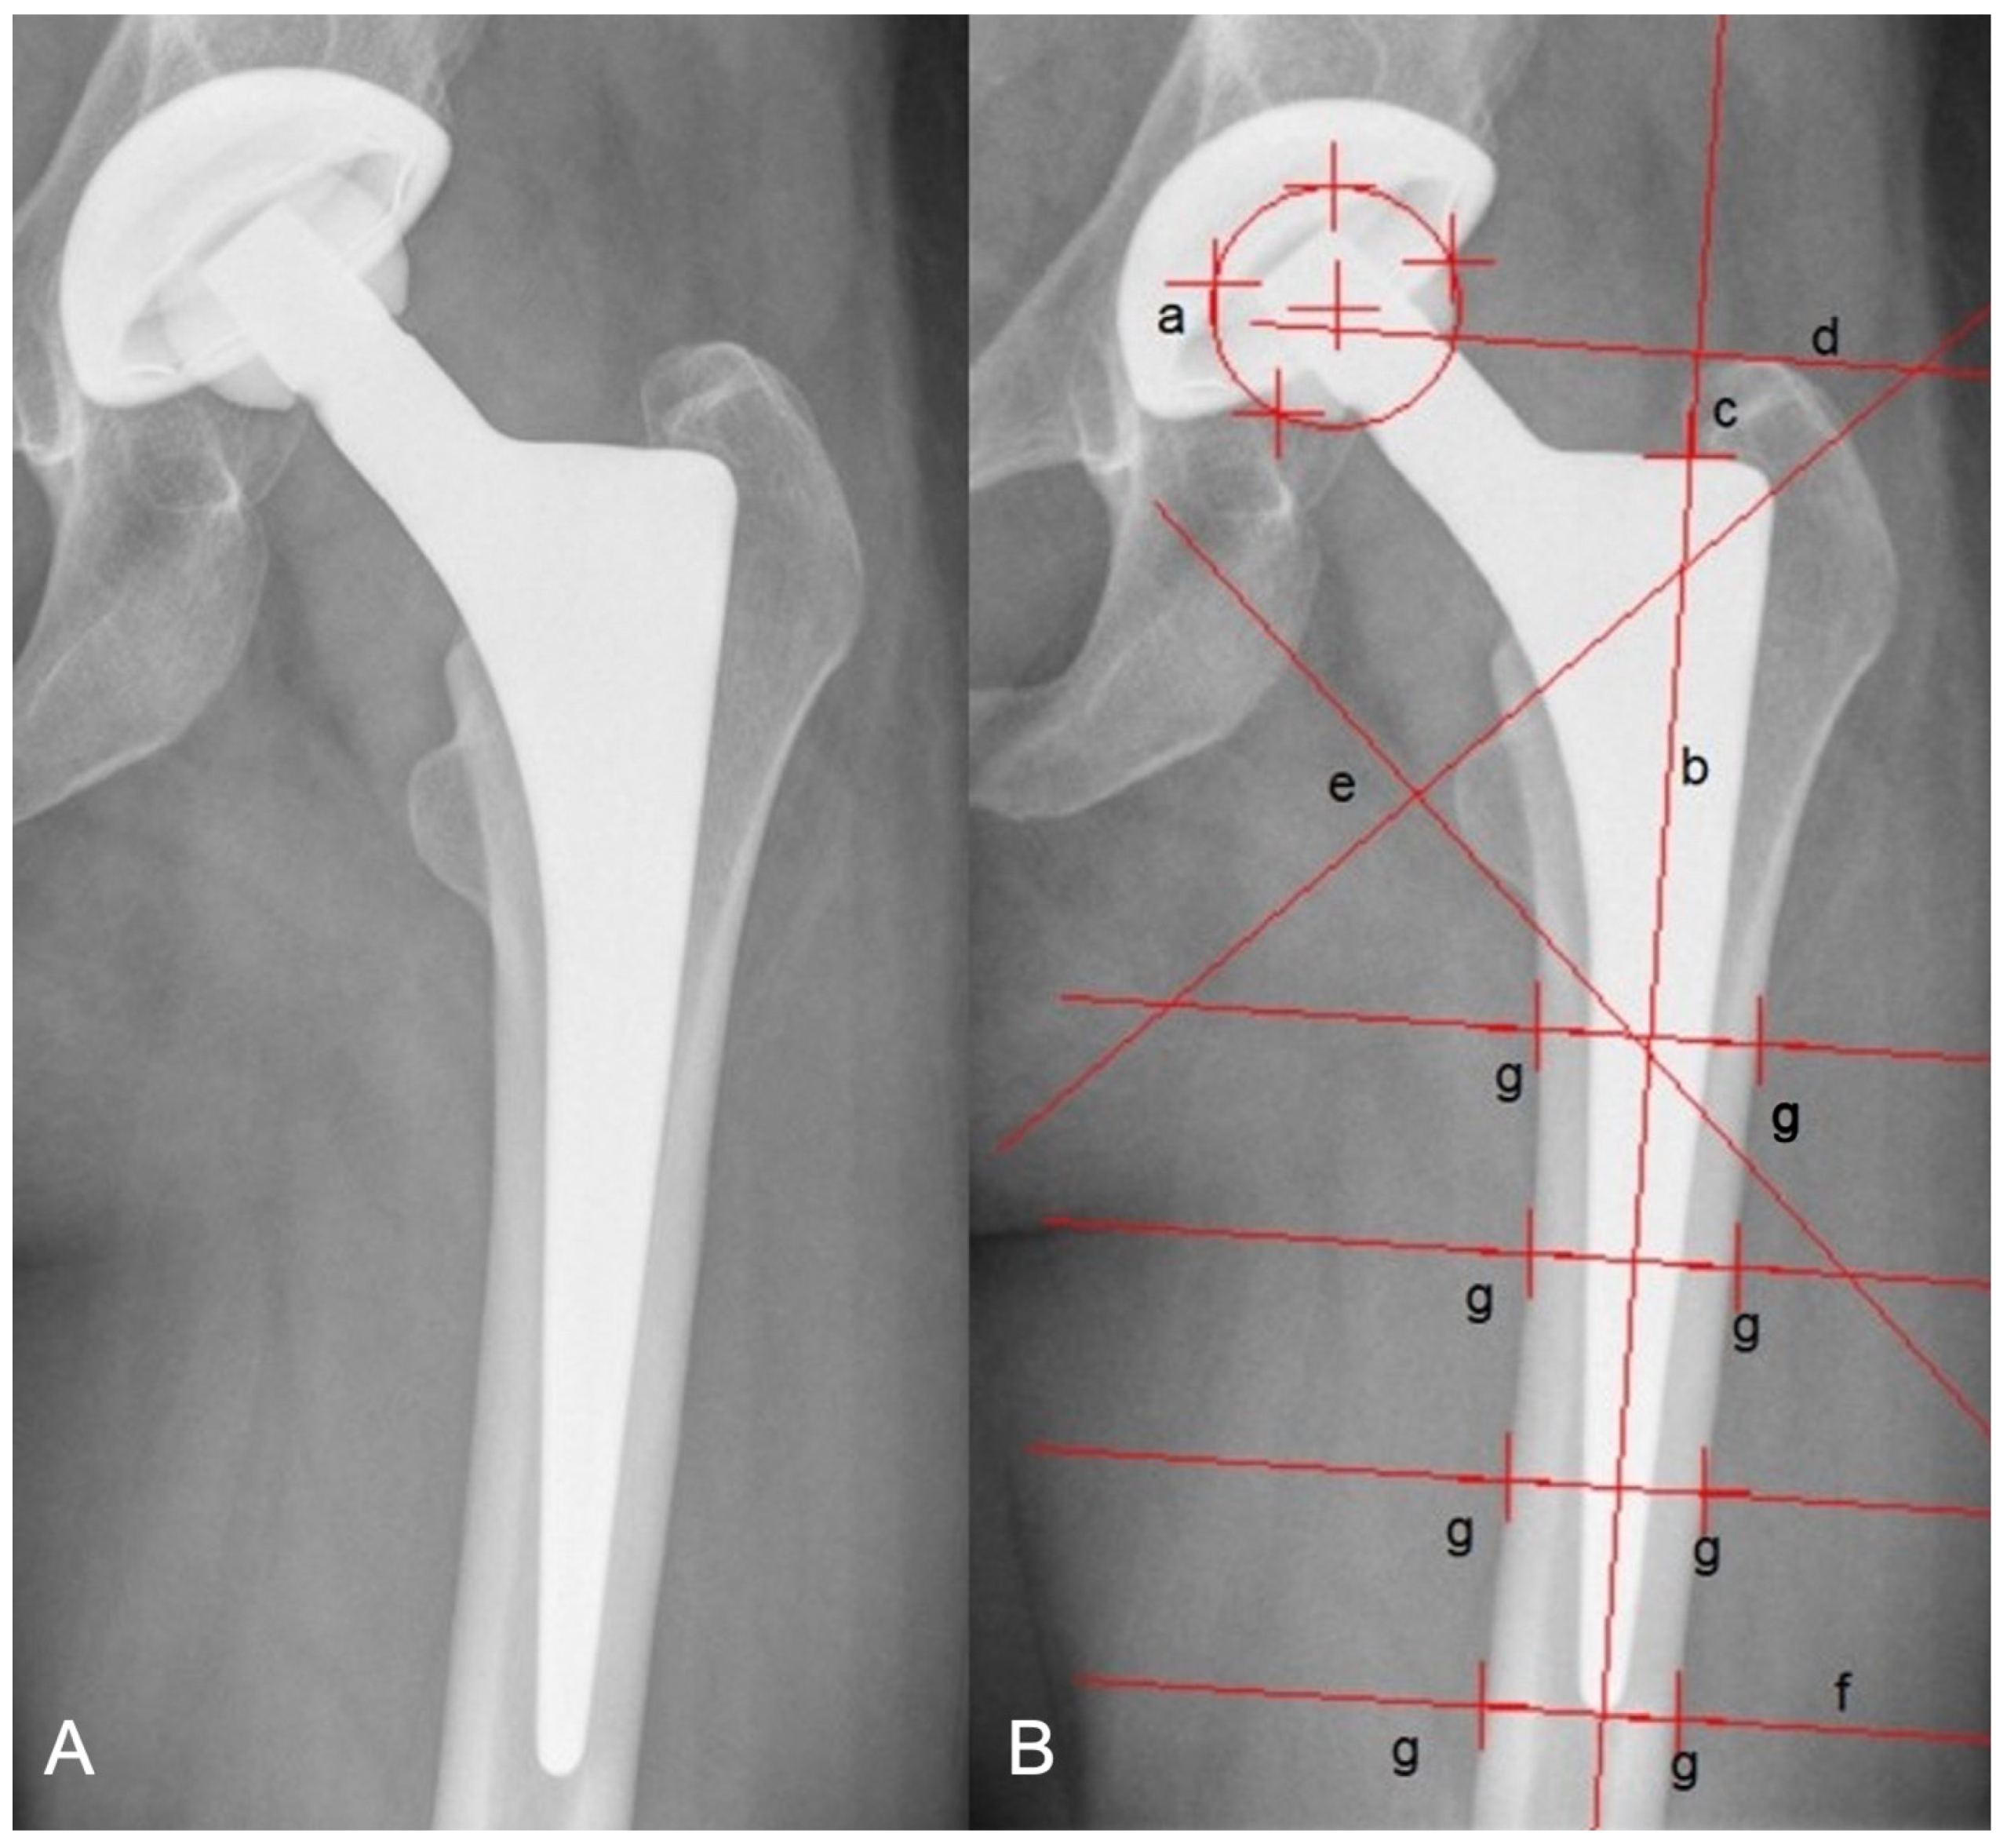

- Gruen, T.A.; McNeice, G.M.; Amstutz, H.C. “Modes of Failure” of Cemented Stem-Type Femoral Components: A Radiographic Analysis of Loosening. Clin. Orthop. Relat. Res. 1979, 141, 17–27. [Google Scholar] [CrossRef]